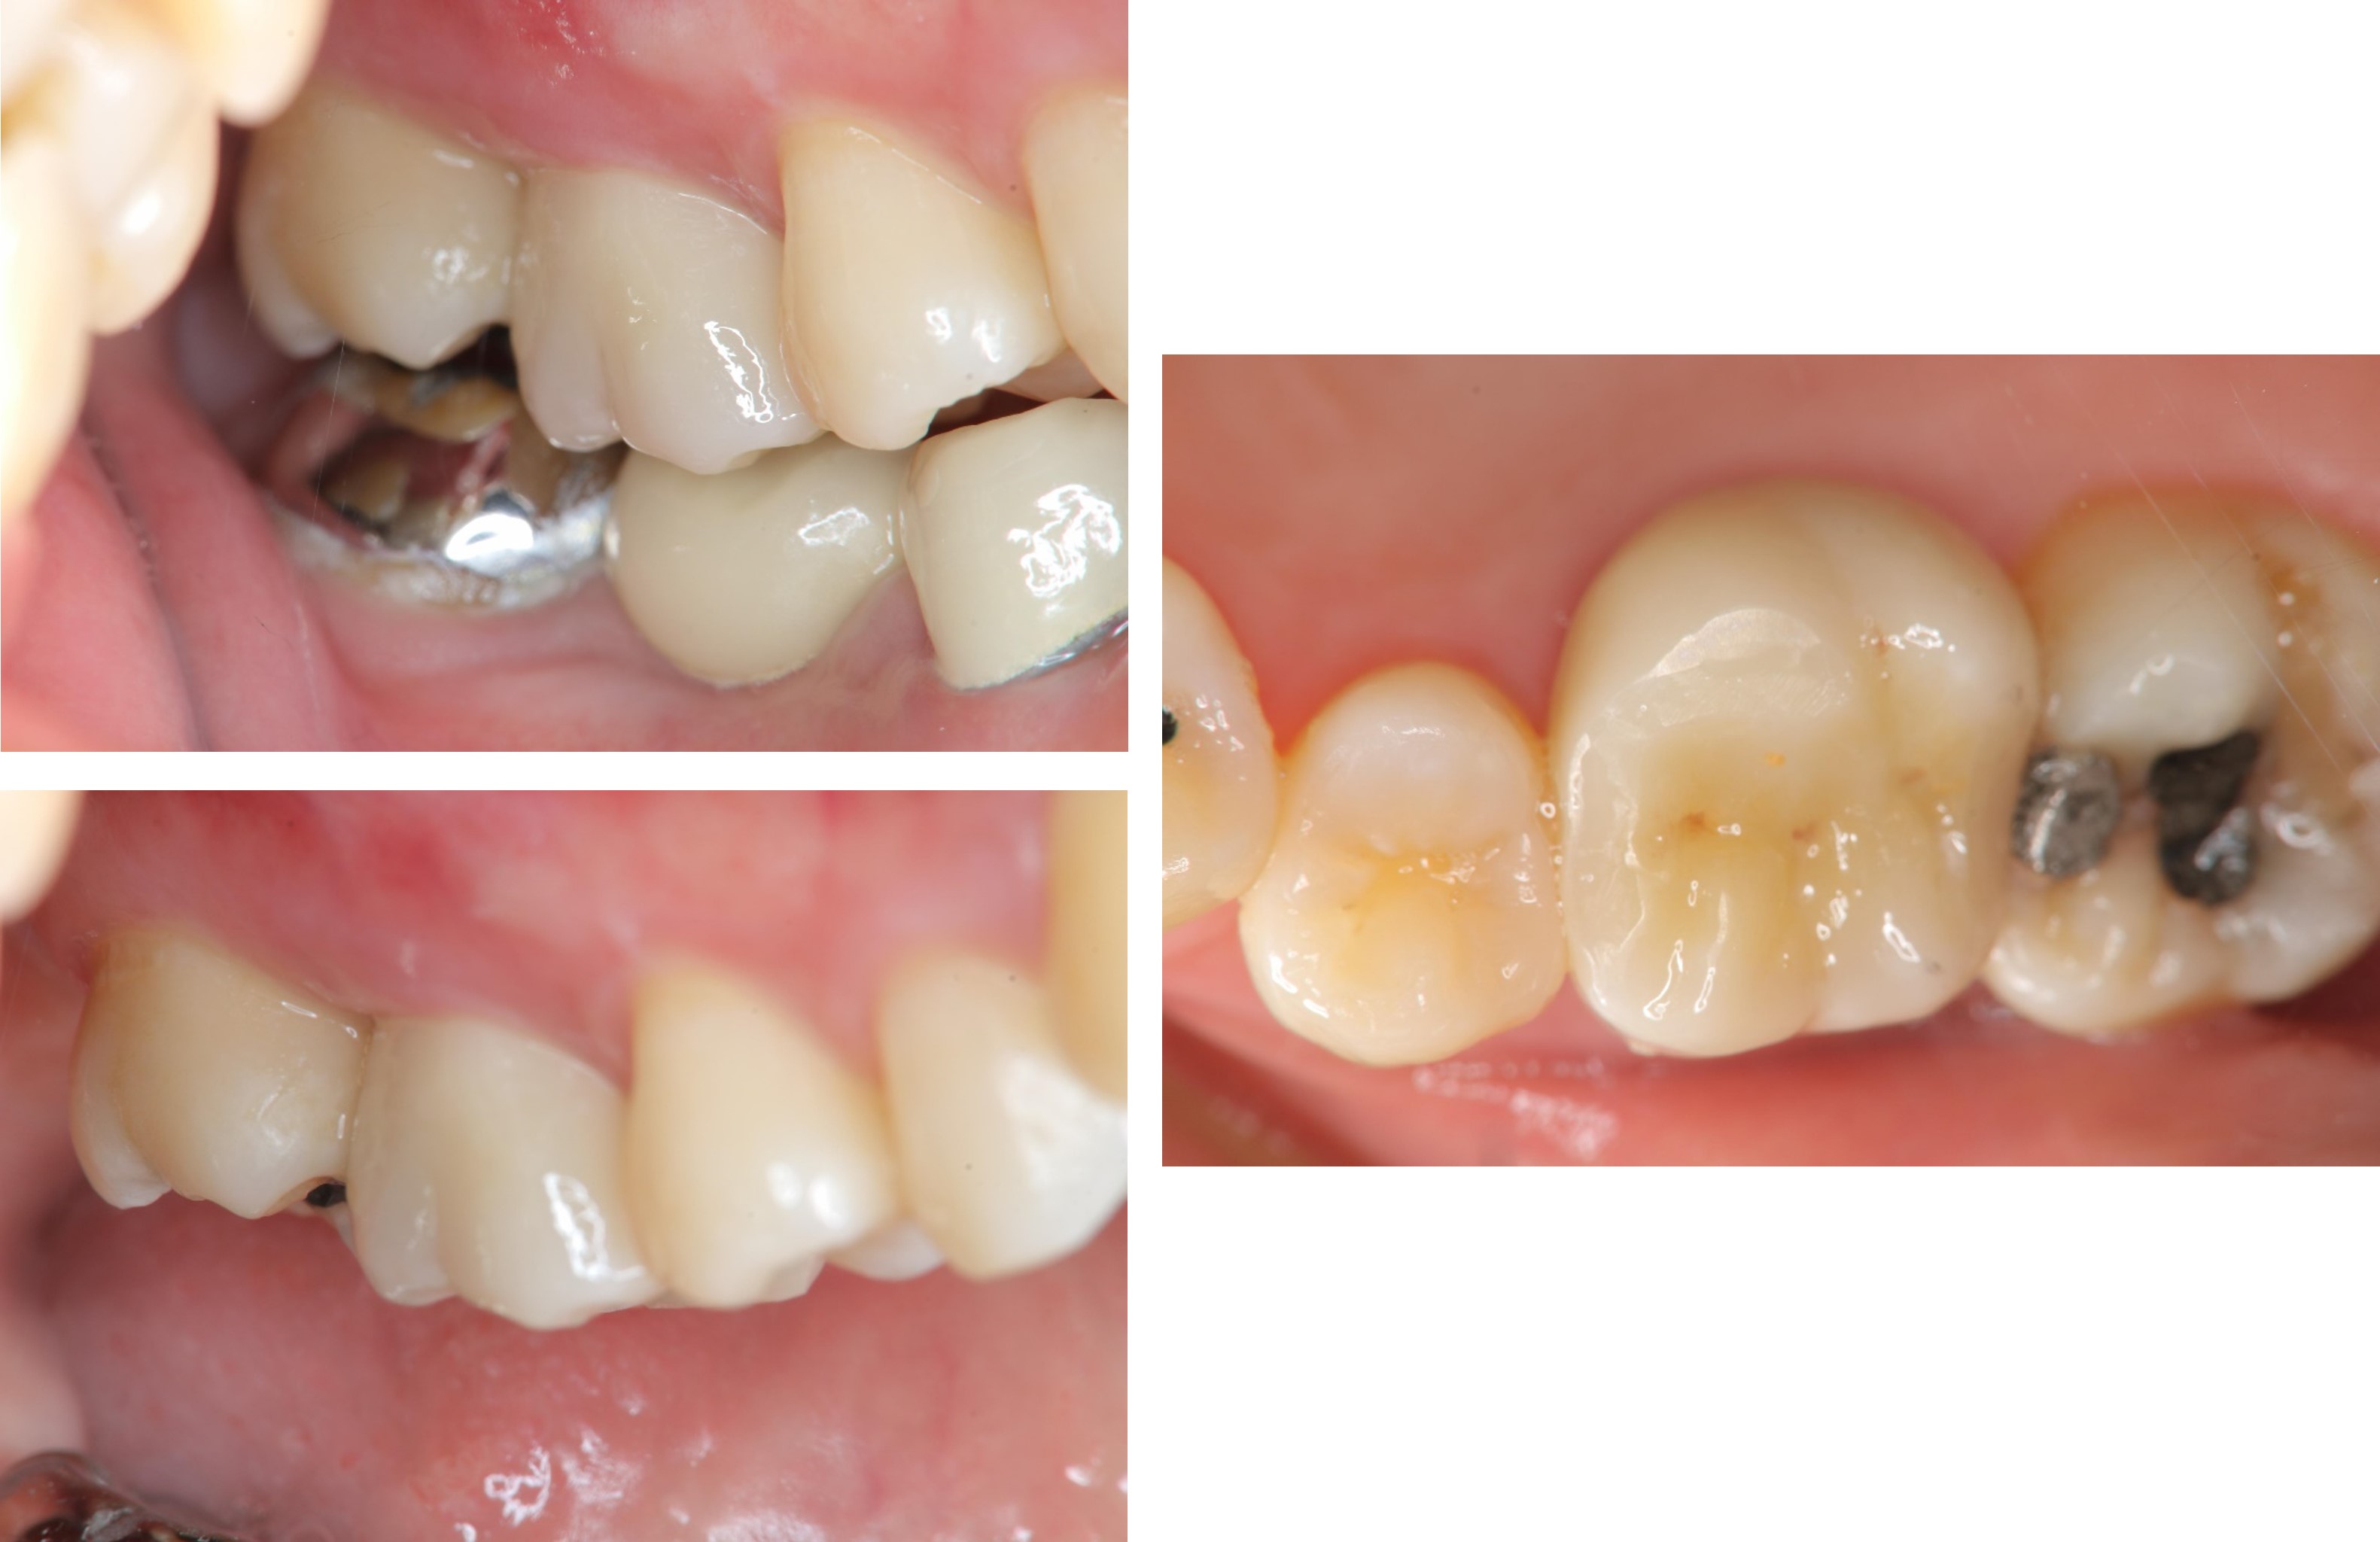

治療前,右上第一大臼齒疼痛

治療前,第一大臼齒蛀牙

膺復前評估牙齦、牙齒狀態

照相比色